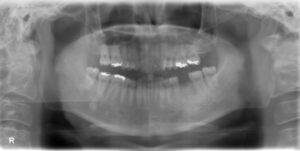

下顎大臼歯1本欠損症例

BEFORE AFTER 36歳男性/下1本欠損/インプラント埋込手術 【治療内容】 左下の奥歯に膿がたまっているという…